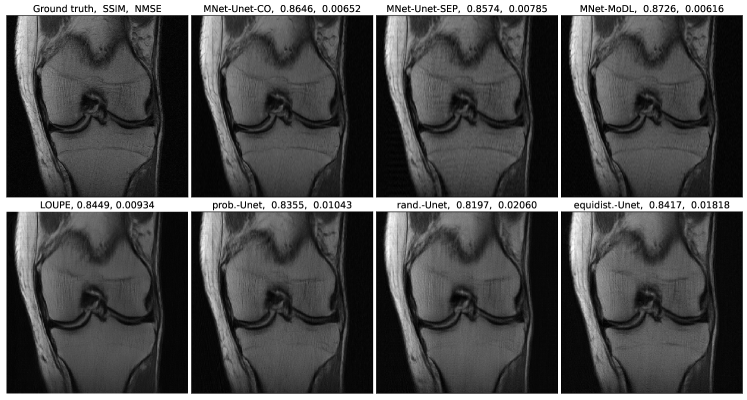

Refer to caption

Figure 7: Reconstruction results from various combinations of sampler-reconstructor pairs with 4×\times acceleration of k𝑘k-space.

Table 2: Reconstruction accuracy comparisons at 4×\times acceleration for various sampler-reconstructor combinations. The values in the table are mean values of each box in Figure 9.

Figure 9: Comparison of reconstruction accuracy of different sampling-reconstructor combinations with 4×4\times acceleration of k𝑘k-space.

Figures 7, 8, and 9 show the reconstruction examples, adaptive or compared mask examples, and reconstruction accuracy comparison results, respectively for the 4×\times acceleration case. The performance trend between methods in the 4×\times acceleration setting is similar to that for the 8×\times acceleration case discussed above. Tables 1 and 2 show the mean reconstruction accuracy comparison between various sampler-reconstructor combinations.

We observe more concentration of the adaptive mask in the region of lower frequencies in the 4×\times acceleration setting. We have also experimented on another 4×\times acceleration setting where we start with 8 lowest frequencies and sample 72 high frequencies. The mask output by MNet has similar patterns as in Figure 8.